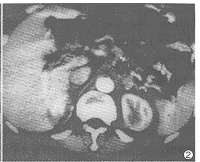

12例CT扫描均见胰腺实质内肿块形成。11例肿块位于胰头部,1例位于胰体部。6例为类圆形,直径为2.5~3cm,4例直径3.5~4cm,边缘规则,较均质,平扫CT值40~60HU,强化后70~110HU,与胰腺实质类似(图1)。2例直径大于4cm,密度不均,内见液化坏死灶,边缘不规则(图2)。8例见肿块内钙化(图3)。7例肿块B超表现为低回声,5例为不均匀回声。

图2 胰尾肿块大小为4.5cm×5cm×6cm,密度不均,中央见液化坏死灶,边缘不规则